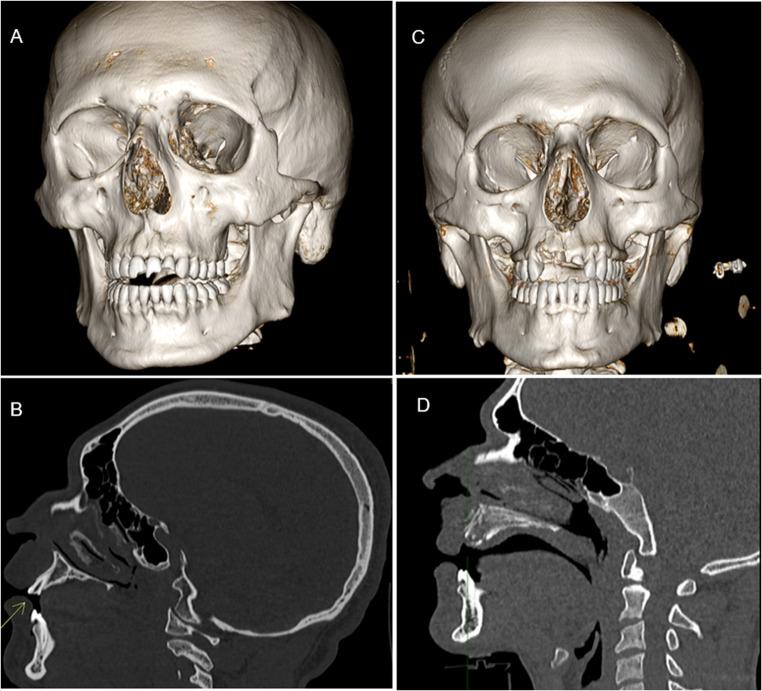

This retrospective study included 611 patients who underwent TBCT following high-energy trauma between July 2024 and February 2025. DTMI findings were analyzed based on initial radiology reports and retrospective image review.

DTMI was identified in 124 of 611 patients (20.2%), of which only 76 cases (61%) were reported at admission. Dental trauma was significantly underreported (76% missed rate), with only 12 of 50 cases (24%) initially recognized. In contrast, maxillofacial injuries were detected in 75 of 97 cases (77,3%). Most DTMI-positive patients (82/124, 66%) had additional traumatic findings, including cranial or spinal injuries (33/124, 26.6%) and multi-district trauma (29/124, 23.4%). Only 20 patients (16%) presented with isolated facial trauma. A small subgroup (18/124, 14.5%) had DTMI with no other traumatic findings, suggesting possible oversight in the absence of overt injury. Underreporting rates were slightly higher during night shifts (55%) compared to daytime (48%), though not statistically significant (χ² = 0.654, p > 0.05). DTMI was more common in males (ratio 1.79:1).

611例患者中有124例(20.2%)被诊断为DTMI,其中入院时仅报告了76例(61%)。牙外伤的漏报率显著(漏报率76%),50例中仅12例(24%)最初被识别。相比之下,97例中的75例(77.3%)被检测出颌面损伤。大多数DTMI阳性患者(82/124,66%)有其他创伤性发现,包括颅脑或脊柱损伤(33/124,26.6%)和多部位创伤(29/124,23.4%)。仅有20例患者(16%)表现为孤立性面部创伤。一小部分亚组(18/124,14.5%)有DTMI但无其他创伤性发现,提示在无明显损伤时可能存在漏诊。夜班期间的漏报率(55%)略高于白班(48%),但差异无统计学意义(χ² = 0.654,p>0.05)。DTMI在男性中更常见(比例为1.79:1)。